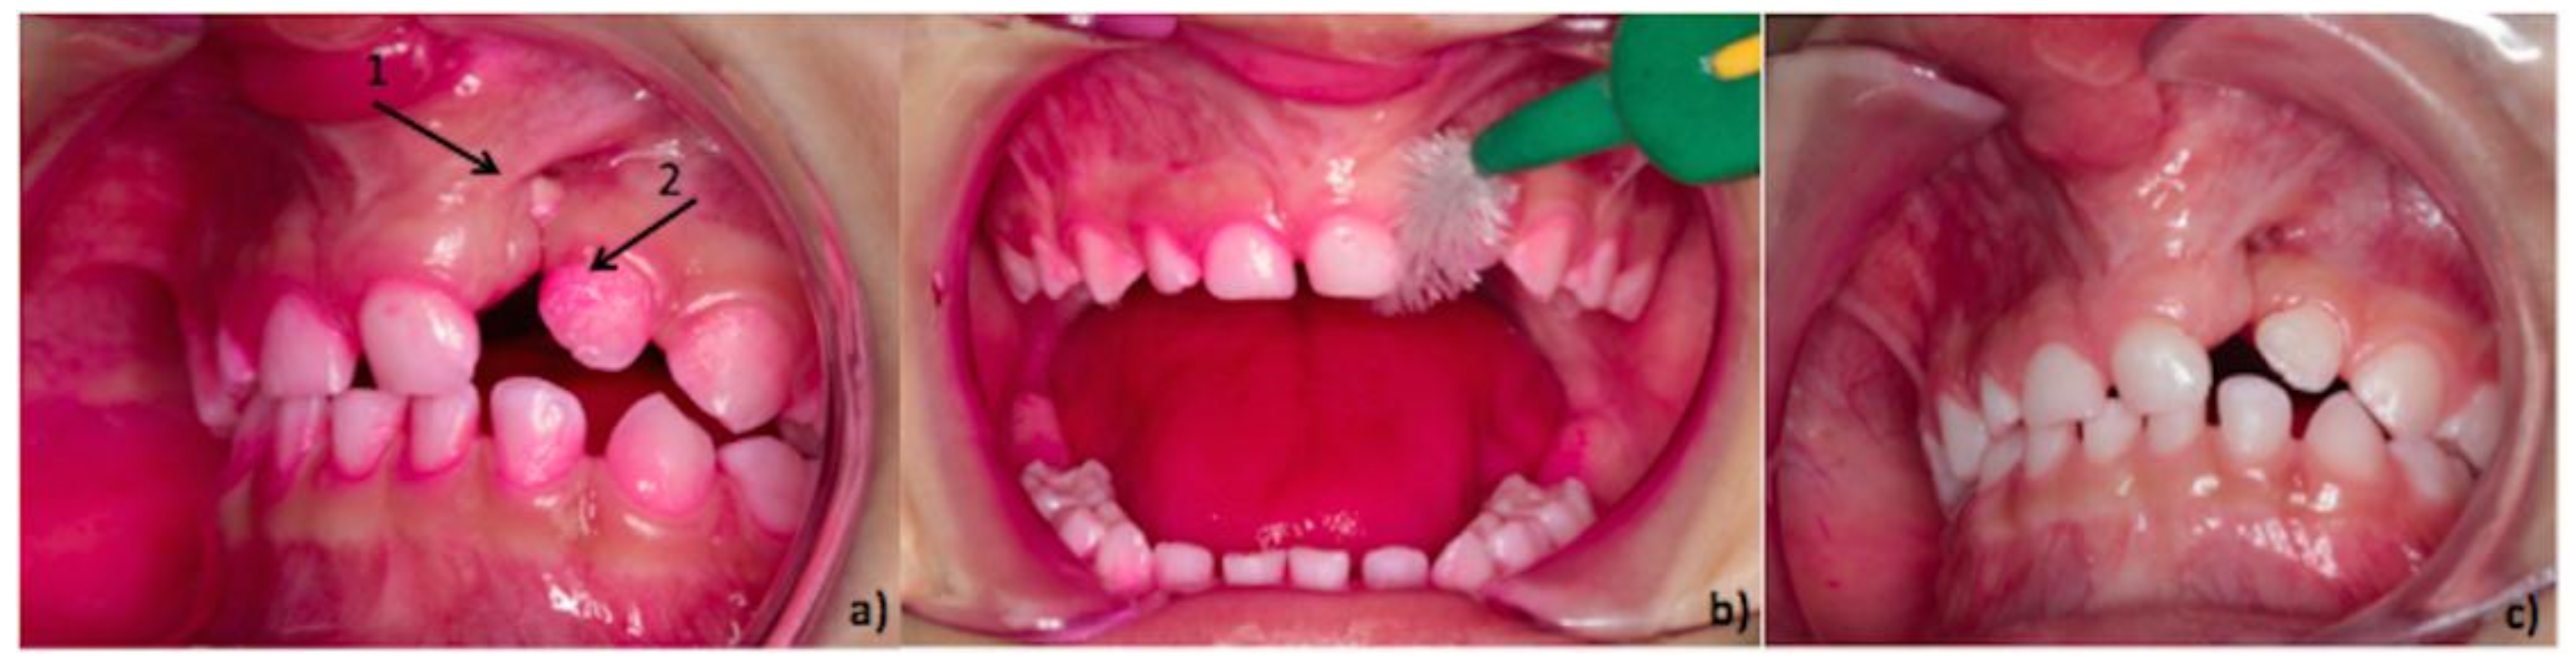

2. Design of the Cleft Toothbrush

3. The Efficacy of the Cleft Toothbrush